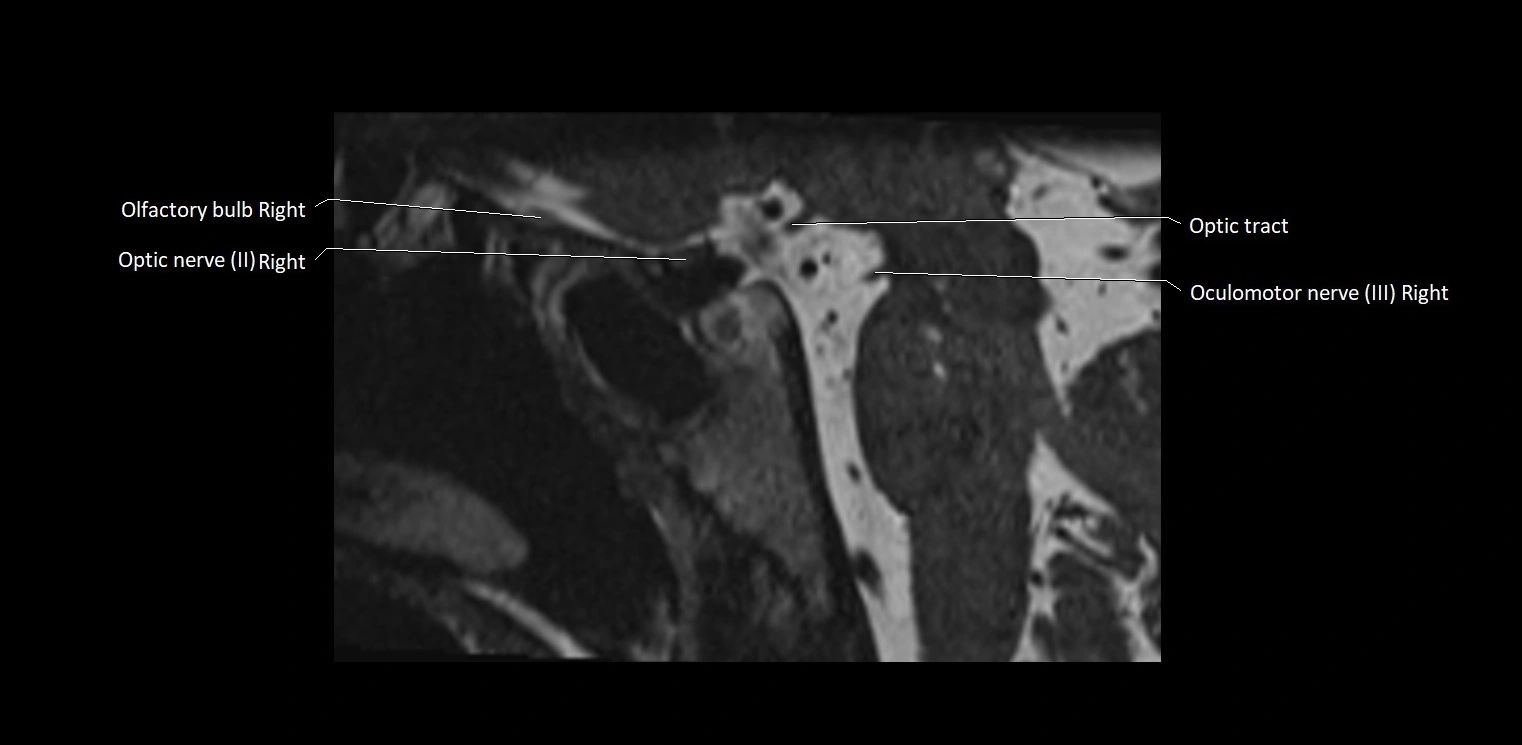

MRI images

image